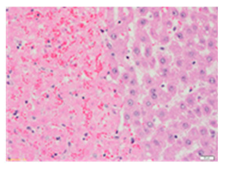

Liver wet weights of all rat groups showed no significant differences (Table 8). According to histochemical hematoxylin and eosin (H&E) staining, treatment with the highest dose of MPE (1000 mg/kg BW) did not result in morphological changes in the liver tissue (B) when compared with DI water treatment (A). Obviously, CCl4 induction (ip)/DI water treatment (po) caused hepatoxicity, which was indicated by a severe degree of fatty changes and fatty cysts in the liver tissue (C), whereas pretreatments of silymarin (100 mg/kg BW, po) effectively decreased the degree of fatty changes and fatty cysts in the liver when compared with the CCl4/DI water group. Indeed, MPE (250 and 1000 mg/kg BW, po) lowered the degree of lipid accumulation in the liver; inversely, MPE (500 mg/kg BW, po) exhibited a severe degree of lipid accumulation. Apparently, taking paracetamol (2 g/kg BW) induced a severe degree of hepatic necrosis when compared with rats that had not received the treatment. Similarly, pretreatments of silymarin (100 mg/kg BW, po) and MPE (250 and 1000 mg/kg BW, po) revealed a mild degree of hepatic necrosis, while MPE (500 mg/kg BW, po) revealed a moderate to severe degree of hepatic necrosis. Accordingly, the findings imply that the consumption of MPE (1000 mg/kg BW) was not harmful to the liver of healthy rats, while MPE (250 mg/kg BW) did improve fat deposition in the livers of CCl4-fed rats and offered protection against liver cell damage in paracetamol-fed rats.

Wet weight values (mean ± SD) and H&E staining of liver from rats with hepatotoxicity induced by CCl4 and paracetamol.